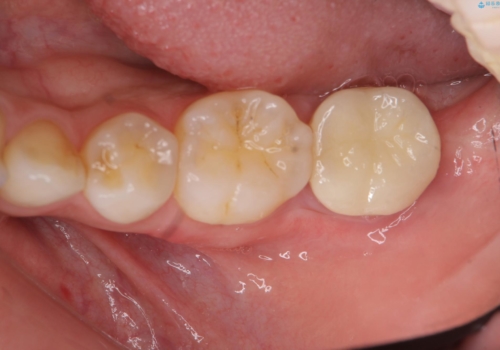

4:歯ぐきが少し落ち着いたところで仮歯にする

5:手術から5ヶ月待って、最終形成を行う

6:歯型をとり、クラウンを作成、仮着する

7:色、形、咬みごこち等問題なければクラウンを本セットする